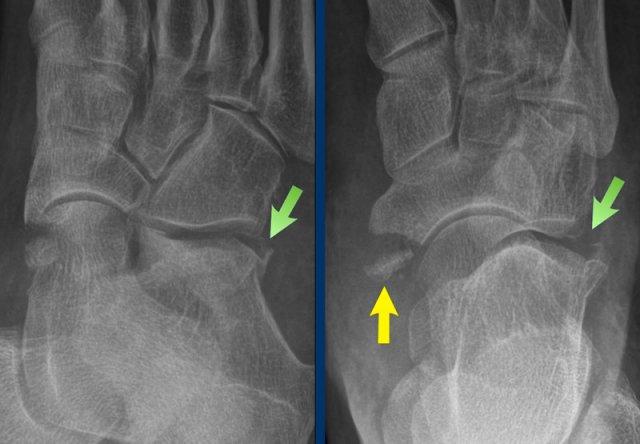

case 3 – distortion

The findings are:

- Avulsion of the medial pole of navicular bone

- Fracture on the lateral side of the calcaneus

Điều này có nghĩa là có một tổn thương ở khớp Chopart, khớp này có hình chữ S và được tạo thành bởi khớp nối giữa xương gót với xương hộp và khớp nối giữa xương sên với xương thuyền.

Các cử động ở khớp này rộng hơn so với các khớp cổ chân khác và bao gồm một loại chuyển động xoay với bàn chân được đưa về phía trong (lật trong) hoặc về phía ngoài (lật ngoài).

Nghịch chuyển dẫn đến phân tâm khớp gót-hộp theo kiểu nén ép và khớp sên-thuyền thường kèm theo gấp lòng, điều này cũng có thể dẫn đến bong gân giật ở mặt lưng của khớp sên-thuyền.

Lộn ngoài dẫn đến sự giãn cách ở phía khớp sên-thuyền với hoặc là đứt rời gân cơ chày sau hoặc là gãy xương do bong gân và sự nén ép ở phía khớp gót-hộp (gãy kiểu kẹp hạt).

Điều này có nghĩa là khi bạn thấy một gãy xương, có thể còn có nhiều gãy xương khác kết hợp với đứt dây chằng và các mảnh avulsion nhỏ.

Trong trường hợp này, có sự lật ngoài kèm giãn cách ở phía khớp sên-thuyền với avulsion cực trong của xương thuyền (mũi tên vàng) và lực nén ở phía khớp gót-hộp dẫn đến gãy xương kiểu kẹp hạt (mũi tên trắng).